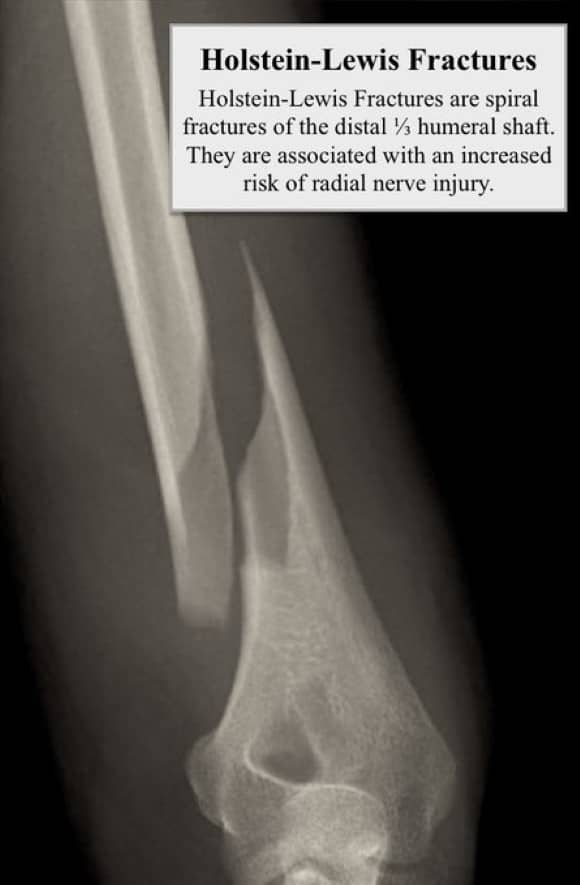

In a 2008 @JofOrthoTrauma study, Ekholm et al again showed that radial nerve palsy was more common in Holstein-Lewis fractures, 6/27 (22%) compared with 27/334 (8%) in other fracture types.

Holstein-Lewis fractures account for 3.8-7.5% of humeral shaft fractures.